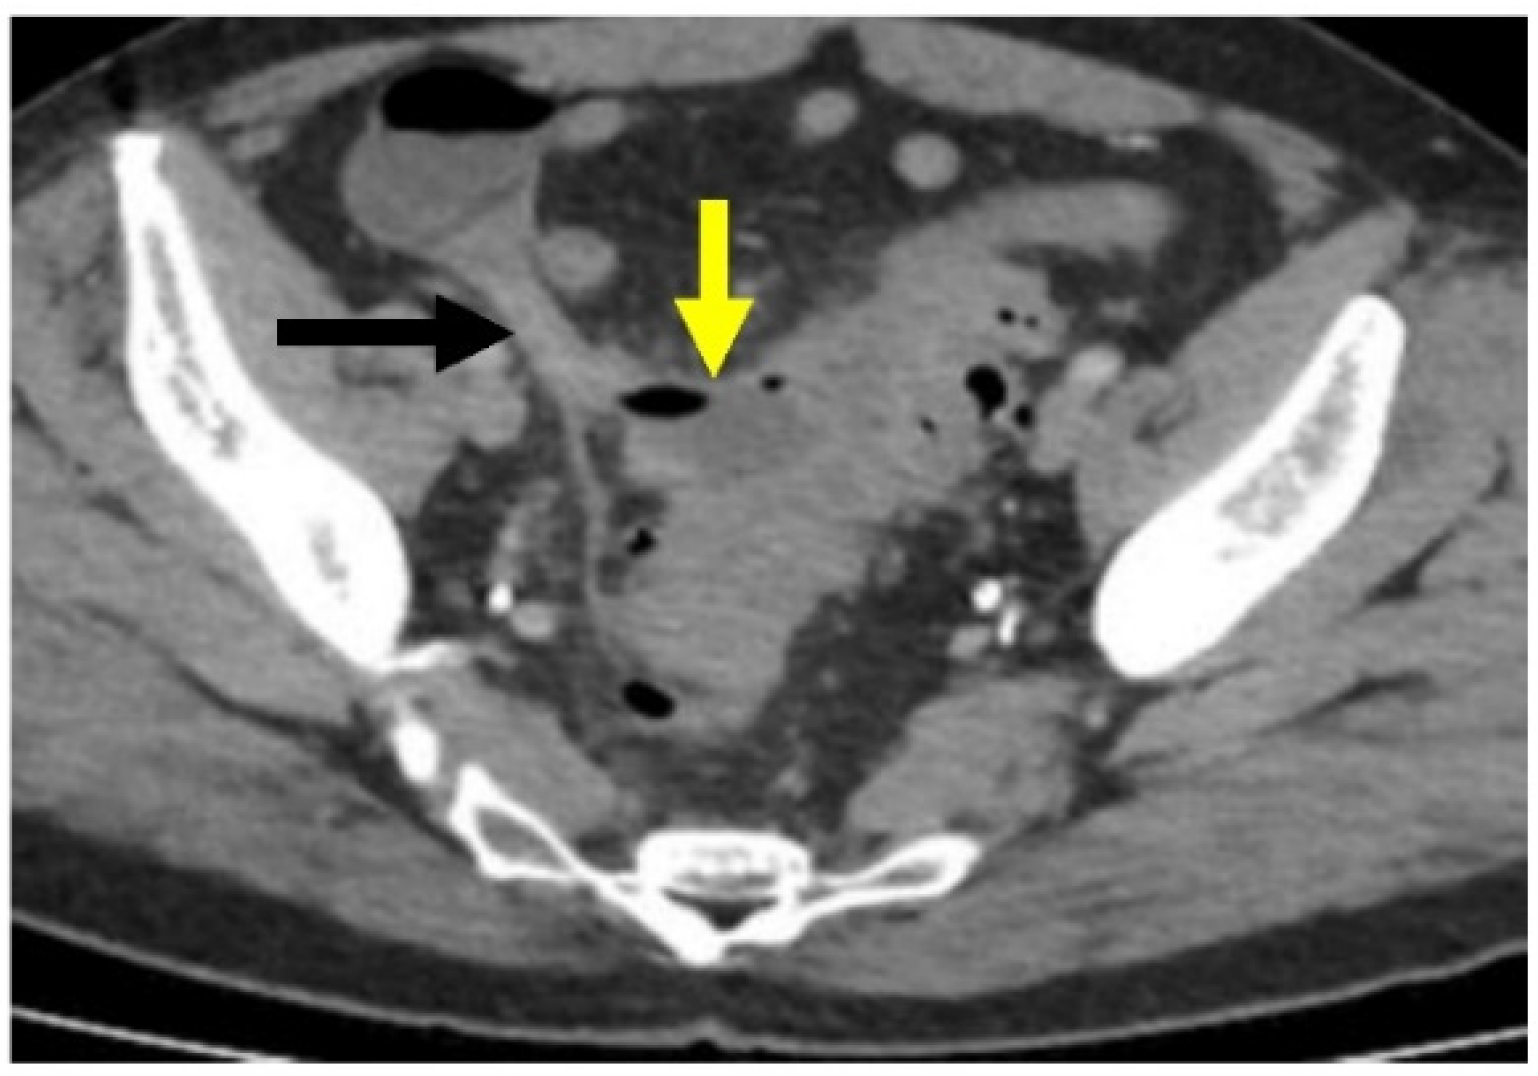

- Minordi, L.M.; Larosa, L.; Berte, G.; Pecere, S.; Manfredi, R. CT of the acute colonic diverticulitis: A pictorial essay. Diagn. Interv. Radiol. 2020, 26, 546–551. [Google Scholar] [CrossRef] [PubMed]